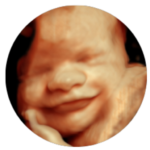

Dr. Jasbir (Bobby) Wallia

MBBS, D.M.R.D

Senior Radiologist

Dr LM Pancholia - X-Ray & Sonography Clinic